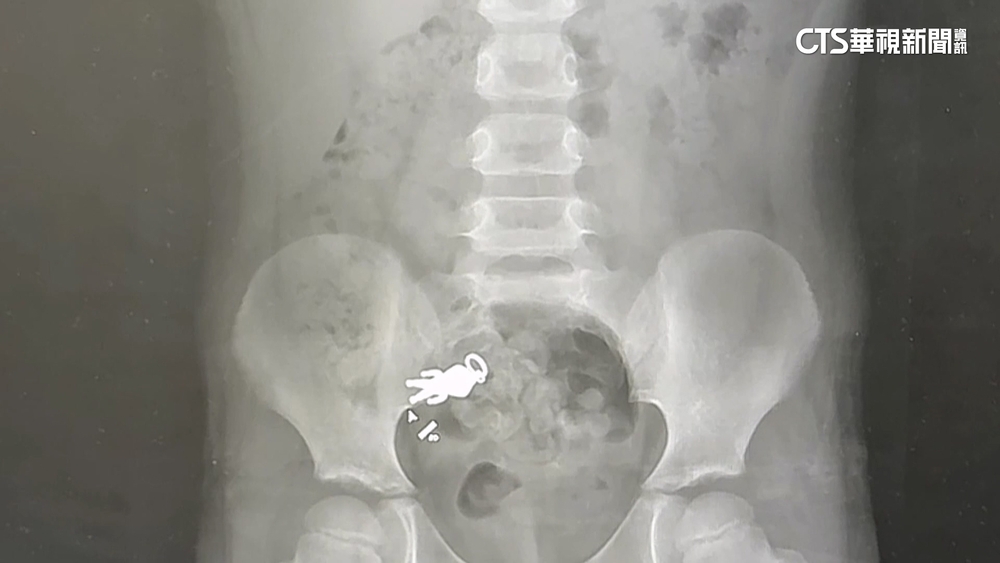

超人力霸王「任務完成」 宜蘭童誤吞吊飾最新照曝光

在社群平台上引發網友熱烈討論的,宜蘭男童與「超人力霸王」的「合體X光照」,昨(9)日晚終於有了最新的進展。

歷經了漫長的等待,這一隻「超人力霸王」終於在昨晚順利排出男童體外,男童叔叔也幽默表示,「超人力霸王」任務完成回來了。不少網友熱情留言,恭喜「超人力霸王」再度重生,還說終於等到完美的結局。